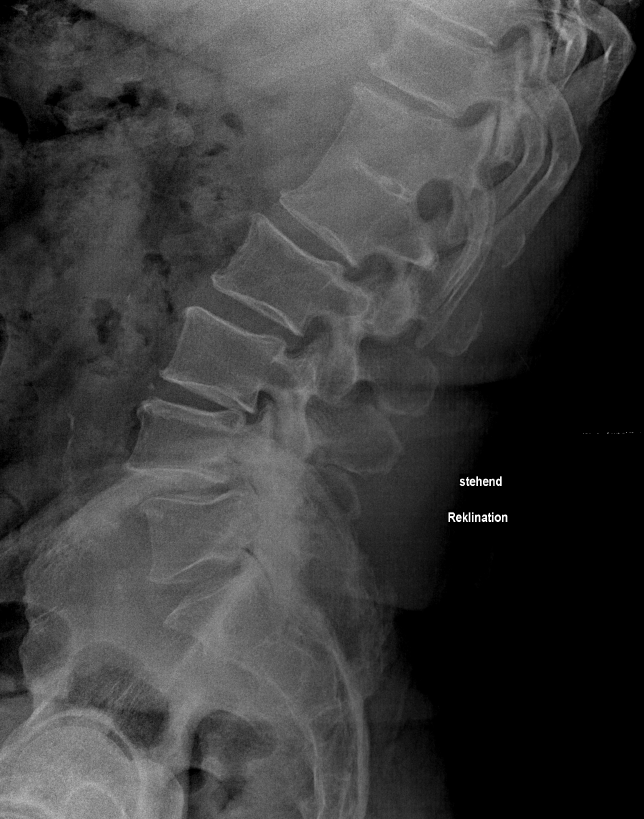

Reklination LWS

Seitliche Röntgenaufnahme einer reklinierten Lendenwirbelsäule.